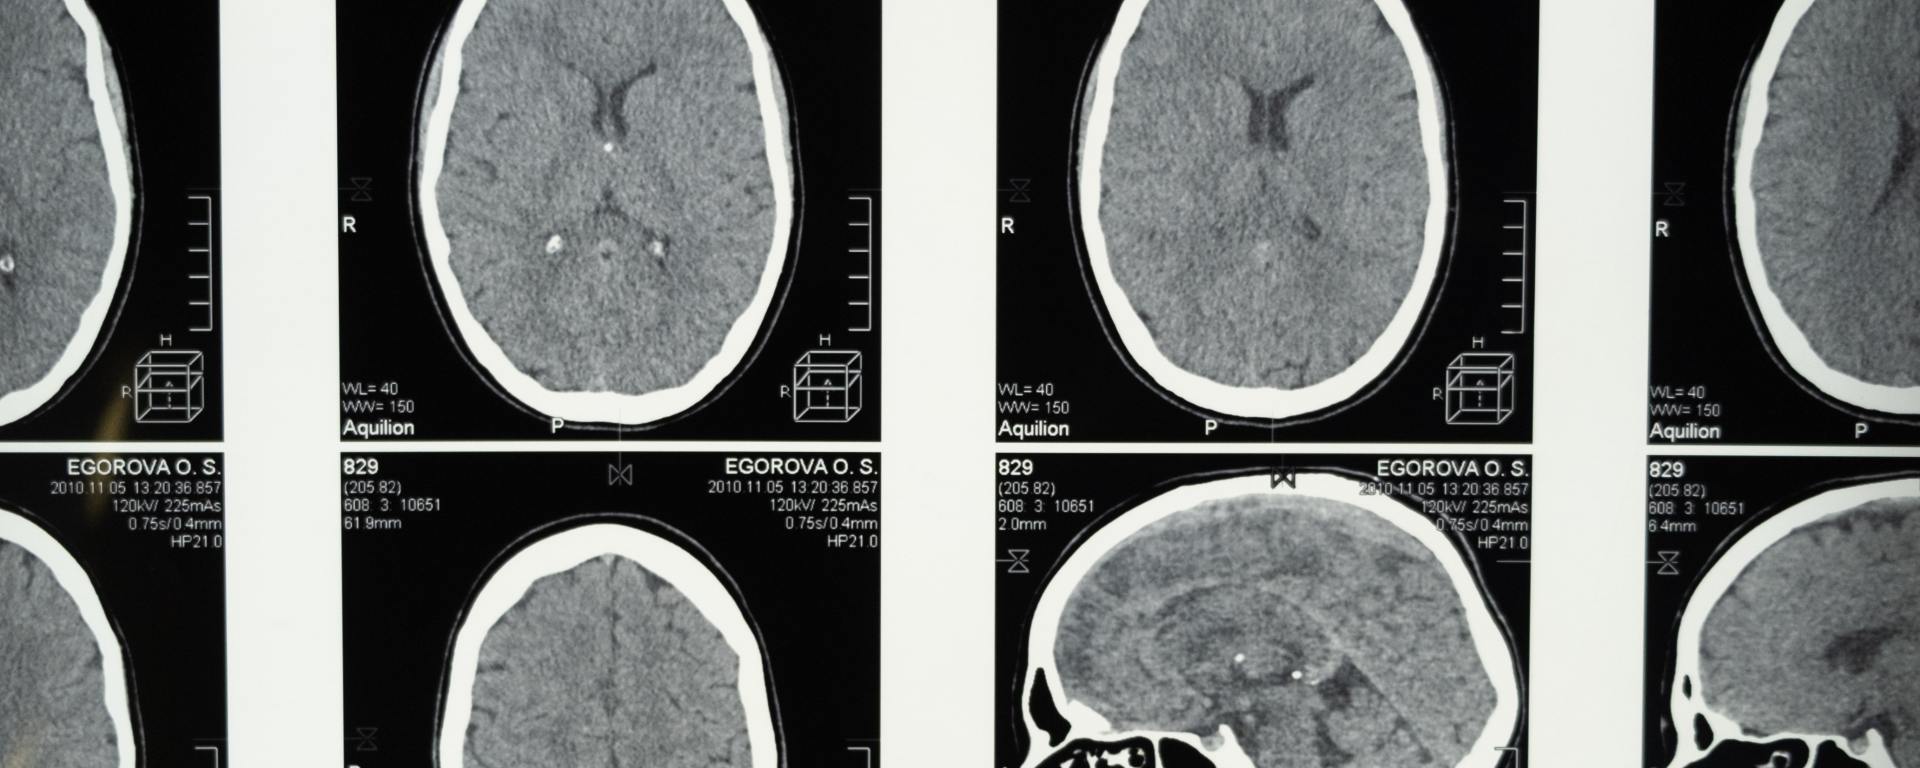

To conduct this study, the researchers recruited one control subject and five patients who became comatose after suffering severe traumatic brain injury due to seizures. Patients were implanted with a ten-contact stereotactic depth electrode to detect seizures and provide antiepileptic treatment, preventing excessive rapid firing of neurons. Single-pulse stimulation—a technique that stimulates specific brain regions by applying a single, brief electrical pulse—was applied to contacts within the ACC (anterior cingulate cortex) and DLPFC (dorsolateral prefrontal cortex), while all other contacts, including scalp and depth electrodes, were recorded. Four of the five patients returned to consciousness during a period ranging from several days to several weeks. The researchers also found that patients who recovered consciousness had a more rapid increase in high-frequency power in the LFPs, particularly in the alpha and beta frequency bands, compared to the patient who did not recover consciousness. This suggests the patients were able to sustain increased levels of relaxation and concentration due to faster alpha and beta frequencies, respectively.